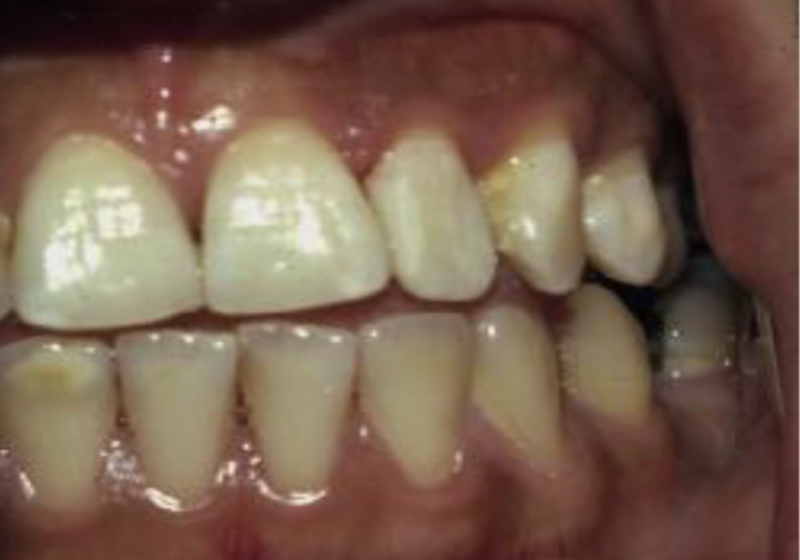

How would you describe this image?

A

Slight demineralization